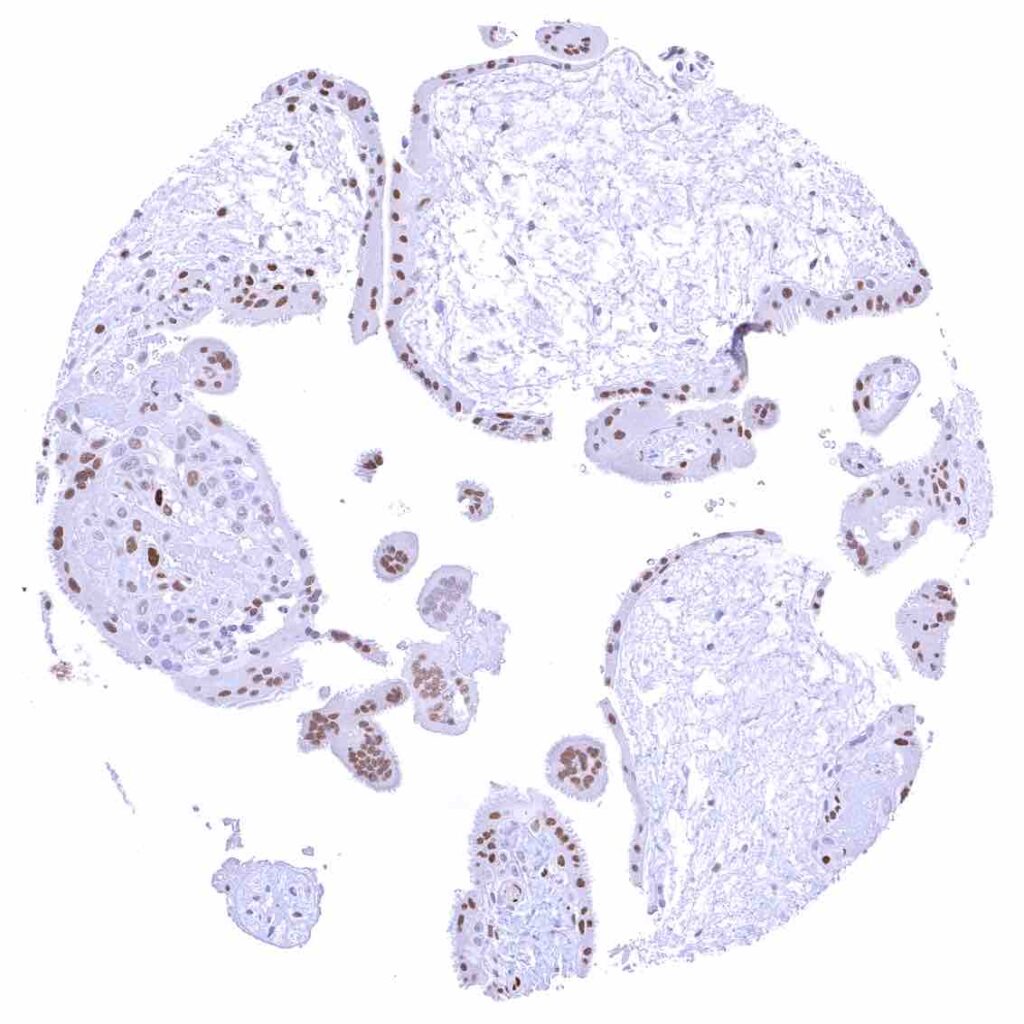

Placenta, early – Strong p27 staining of all nuclei of the syncytiotrophoblast.

Placenta, mature – Weak nuclear p27 staining of trophoblast and stroma cells.